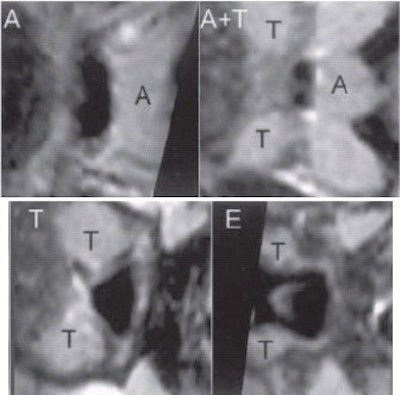

| A gray-level, 2-D scene of the cross section of the airway orthogonal to the centerline at marked locations A (adenoid), A and T (adenoid and tonsil overlap), T (tonsils), and E (epiglottis). |